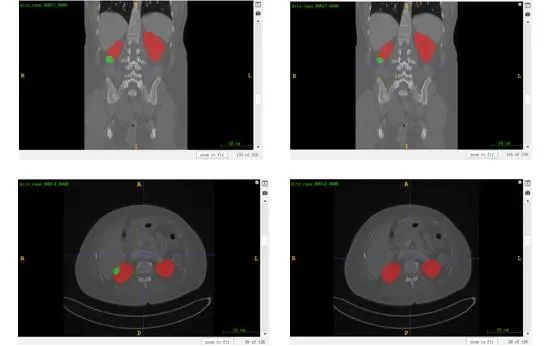

According to the results shown in Figure 2, nnU-Net achieves good performance on kidney segmentation (marked in red), but it fails to detect a small number of tumor segmentation parts (marked in green). Furthermore, the last CT image demonstrates an incorrect identification of the tumor beneath the kidney, which could potentially be attributed to inadequate training.

Figure 2 Visualized results of kidney-tumor segmentation